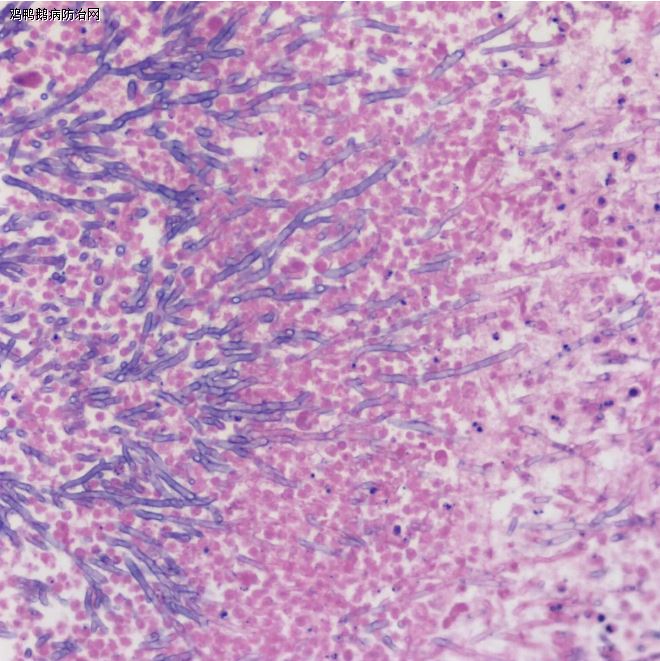

严重的雏鸡霉菌肺炎(来自Merck Vet Manuel)